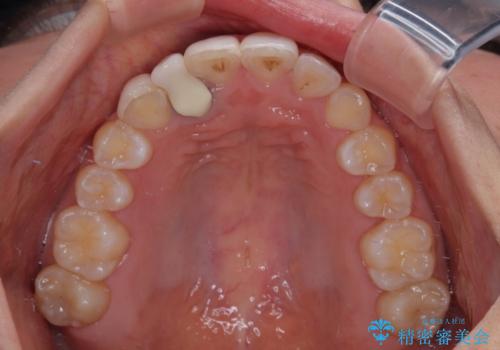

- 上下前歯のデコボコを気にして来院された患者様です。

インビザラインによる上下歯列の拡大と、IPR(歯と歯の間を削る)にるスペースの獲得により、前歯のデコボコを改善することとしました。